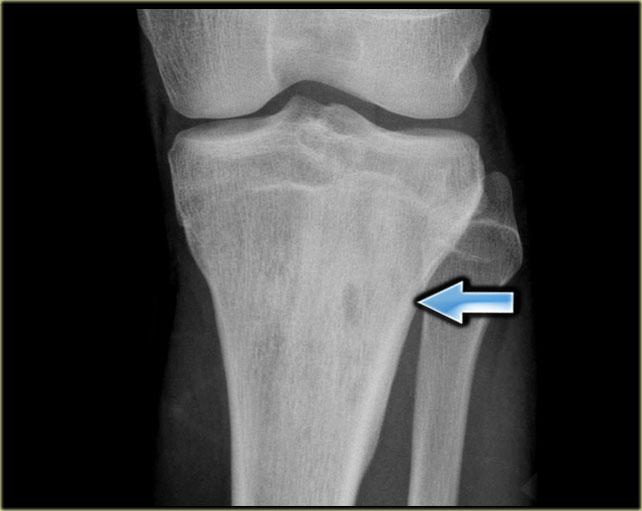

Bên trái là tổn thương tiêu xương không rõ ranh giới ở vùng hành xương đầu gần xương chày với xơ cứng phản ứng lan rộng và phản ứng màng xương dạng đặc.

Bên trái là tổn thương hỗn hợp tiêu xương và xơ cứng ở đầu trên xương cánh tay với phá hủy vỏ xương không đều.

Có phản ứng màng xương xâm lấn và khối phần mềm.